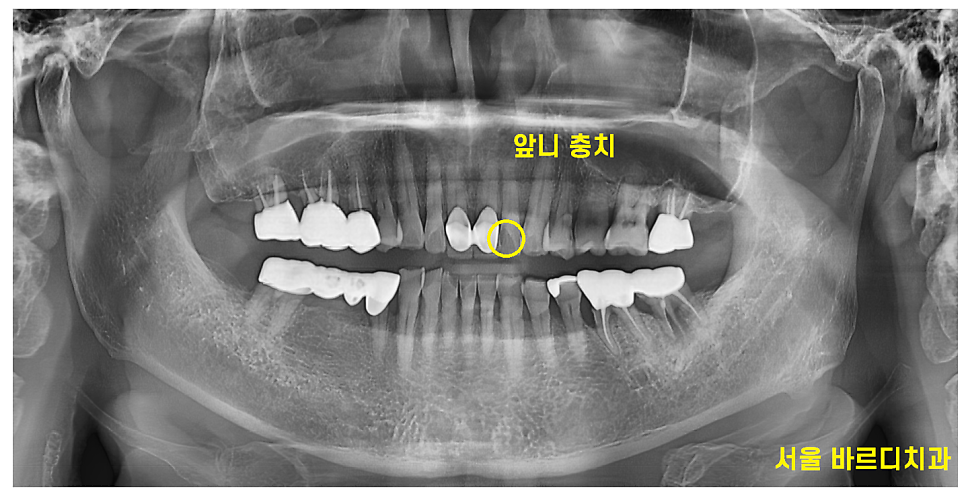

환자분의 동의를 얻어 x-ray를 촬영하였는데

유독 속이 텅 빈 부위가 눈에 띄였습니다.

왼쪽 두번째 앞니 부분에 커다란 충치가 관찰되네요~